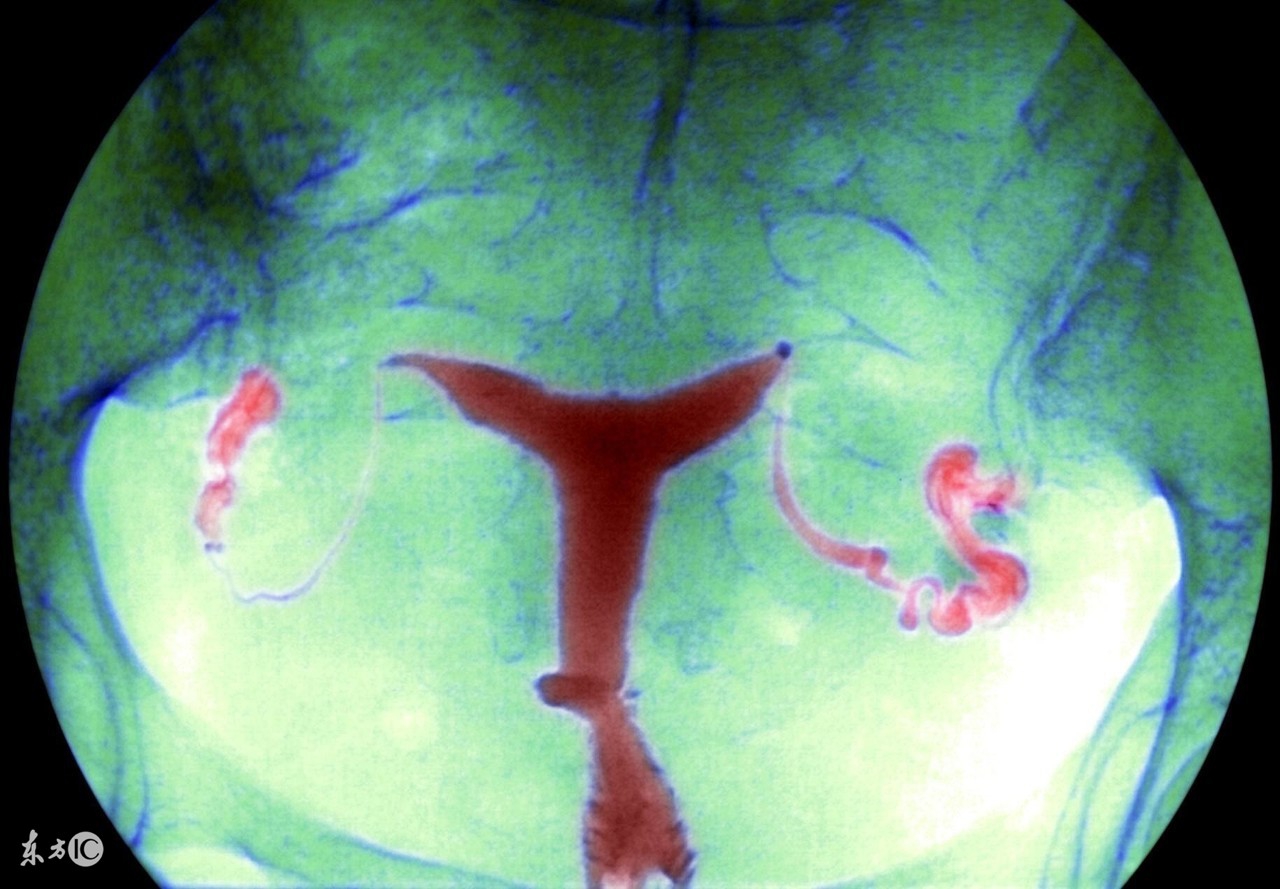

盆腔炎是女性常见的一种疾病,可分为慢性和急性。生活中,慢性盆腔炎比较常见,这种病在病发时可能会伴随着一些低热,病人会觉得自己总是感到疲劳,但是由于全身上下的症状并没有很明显,所以难以引起注意。

慢性盆腔炎可能会引起下腹坠痛,这是盆腔出血或者瘢痕粘连导致,特别是在女性在劳累,月经前后情况会有所加剧。在生活中不乏有女性因为慢性盆腔炎的诊治不及时,最后导致了不孕不育。如果想要预防盆腔炎,就需要做到以下几点: